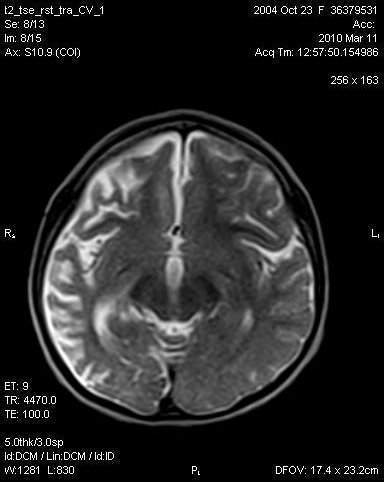

Encefalitis : Paho Who Encefalitis Equina Venezolana / Rare clinical cases have also been reported in other species, such as cattle.. Encephalitis, an inflammation of the brain parenchyma, presents as diffuse and/or focal neuropsychological dysfunction. Rare clinical cases have also been reported in other species, such as cattle. La encefalitis es una enfermedad poco común. Concretamente, cuando la inflamación se refiere al cerebro y a la médula espinal, la patología se denomina encefalitis. ' encefalitis ' komt voor in de woordenlijst nederlandse taal van de taalunie en in de spellingwoordenlijst van opentaal.

Although it primarily involves the brain, the meninges are frequently involved (meningoencephalitis).

The best way to avoid encephalitis is to prevent the illnesses that may lead to it. Muchos casos suceden en una temporada en particular. Early symptoms are fever, sensitivity to light, and headache. Encefalitis er betændelse i hjernen. Entre el 30 y el 50% de las personas con encefalitis pueden sufrir secuelas neurológicas o psiquiátricas permanentes. Although it primarily involves the brain, the meninges are frequently involved (meningoencephalitis). Encefalitises la irritación e hinchazón (inflamación) del cerebro, casi siempre debido a infecciones.causas, incidencia y factores de riesgola encefalitis. Office of communications and public liaison national institute of neurological disorders and stroke national institutes of health bethesda, md 20892. Encephalitis is an acute inflammation of the brain. In these cases, symptoms may include headache, vomiting, fever, confusion and seizures. La encefalitis es un conjunto de enfermedades producidas por una inflamación del encéfalo. Introducción encefalitis por anticuerpos antirreceptor de nmda y otras encefalitis autoinmunes encefalitis autoinmunes en pediatría nuevos mecanismos patogénicos nuevas estrategias terapéuticas y respuesta al tratamiento preguntas pendientes y nuevos problemas. ' encefalitis ' komt voor in de woordenlijst nederlandse taal van de taalunie en in de spellingwoordenlijst van opentaal.